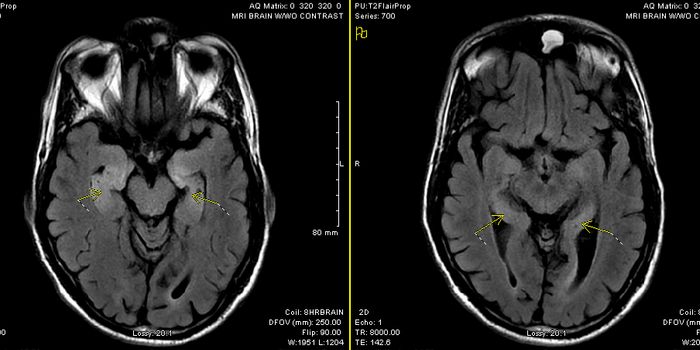

OCT 24, 2015ImmunologyMicroglia hold down the fort in the brain as the primary immune cell presence. When brain disease hits, they get rid of ...

JAN 07, 2022CancerThe blood-brain barrier (BBB) describes the complex vasculature network that delivers oxygen and nutrients to the brain. ...